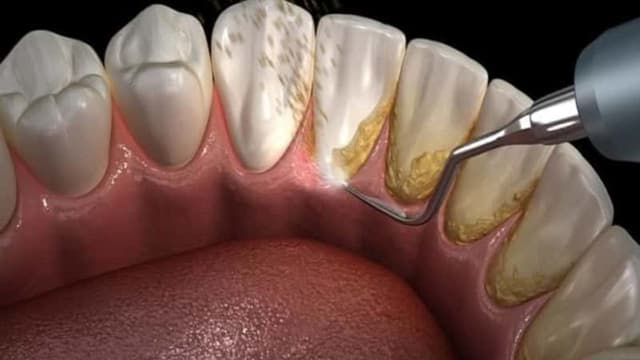

Vôi răng, hay còn gọi là cao răng, là một vấn đề thường gặp và có thể gây ra nhiều hệ lụy cho sức khỏe răng miệng nếu không được xử lý kịp thời. Vôi răng được hình thành do sự tích tụ của mảng bám vi khuẩn và các chất khoáng trong nước bọt. […]

Vệ sinh răng miệng là một trong những yếu tố quan trọng để bảo vệ sức khỏe toàn diện. Trong đó, việc lấy cao răng định kỳ là một phần không thể thiếu. Cao răng, hay còn gọi là vôi răng, được hình thành từ mảng bám thức ăn và vi khuẩn, dần dần tạo […]

Sức khỏe răng miệng có thể ảnh hưởng đến sức khỏe tổng thể và chất lượng cuộc sống của mỗi người. Để duy trì sức khỏe răng miệng, bạn cần thực hiện nhiều biện pháp phòng ngừa và chăm sóc định kỳ, trong đó lấy cao răng là một dịch vụ cơ bản nhưng cực […]